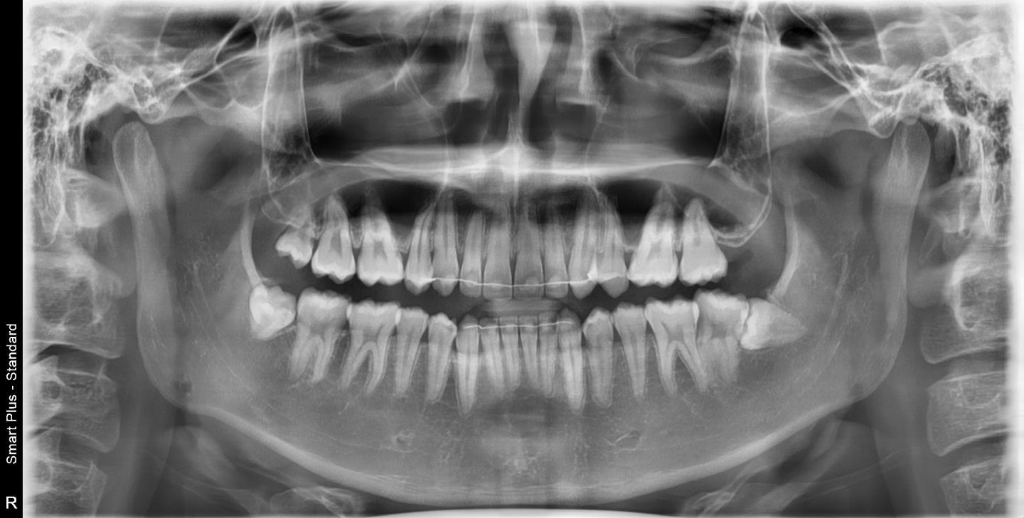

저 상태에서 그냥두면 사랑니 바로옆 어금니를 점점 상하게 하닌 가능한 수평매복 사랑니는 가능한 빨리 뽑는 것을 추천합니다. 반대편 아래사랑니도 매복되어 있으니 이것도 뽑는 것으도 뽑는 것을 추천합니다.

사랑니가 수평 매복 되어있고, 앞의 치아 뿌리와 위치가 가까운 경우 앞 치아의 치근 흡수로 인한 통증이나 염증이 발생할 수 있으므로 증상이 없더라도 예방적 차원에서 발치 해주는 경우가 많습니다

사진상 보이는 사랑니는 썩거나 앞의 치아에 문제를 일으킬 수 있어 웬만하면 뽑으시는 것이 좋겠습니다